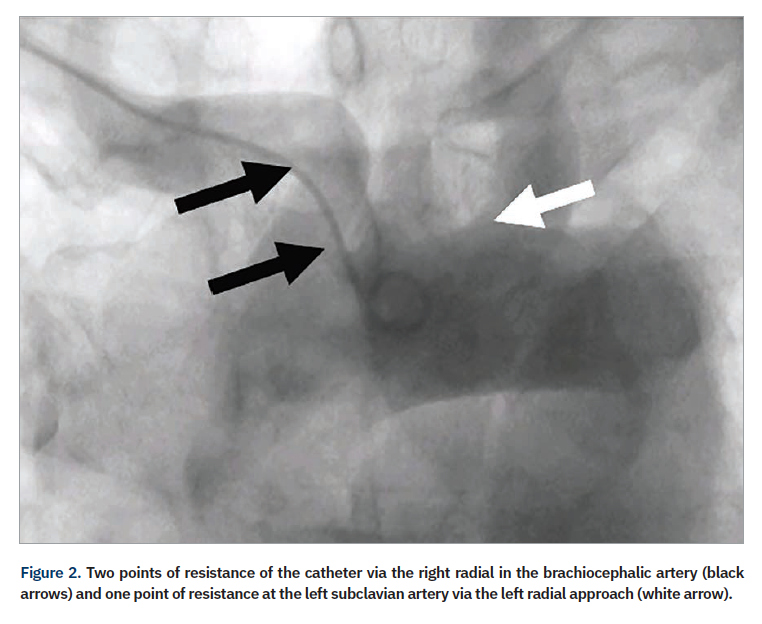

A review of 2100 failed transradial approaches for PCI found age >75 years (P<.001); prior coronary bypass surgery (CABG) (P<.001), and height <5 feet, 5 inches (165 cm) (P=.02) as independent predictors.9 Another study examined 1609 patients and found previous CABG, cardiogenic shock, and female sex as multivariable predictors for transradial failure of PCI (with right radial the default for transradial procedures, except in the case of prior CABG).10 Although a more experienced radial operator will often overcome the challenges of a right radial approach, there are still some patients where the majority of operators favor femoral access, such as patients with history of CABG. In a subgroup of patients (Table 1), access via the left radial artery may allow programs to “stay radial”. The catheter passing via the left arm follows a similar path as the femoral approach, with only one area of resistance in its path, at the left subclavian-aorta junction; conversely, the catheter passing via the right arm has two areas of resistance in its path, at the subclavian-brachiocephalic and the brachiocephalic–aortic junctions (Figure 2).11 An example of the analogy is the ease of right radial in those with situs inversus totalis (Figure 3), where with only one spot of resistance, the typical femoral catheters can be used easily via the right wrist.12